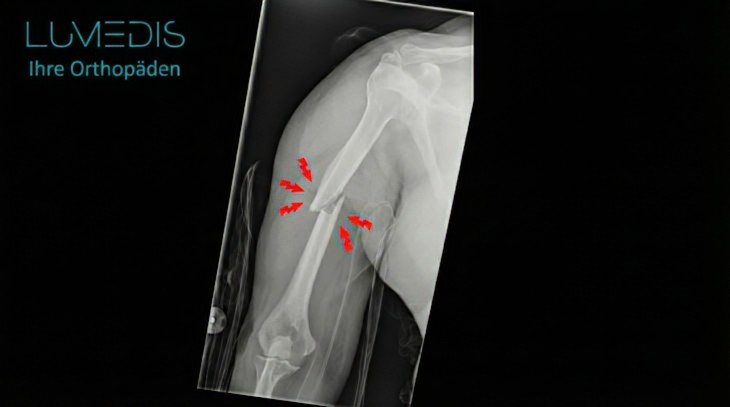

Röntgenbild eines Oberarmbruchs im Schaft vor und nach der OP mit einem Nagel

Röntgenbild eines Oberarmbruch vorher und nach Versorgung mit einem Oberarmnagel

Röntgenbild eines Oberarmbruchs links

Röntgenbild eines Oberarmbruchs im Schaftbereich